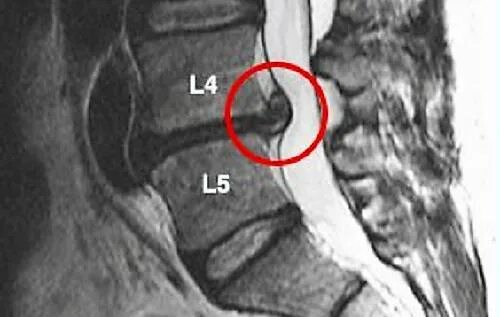

Грыжа диска 0.5 см